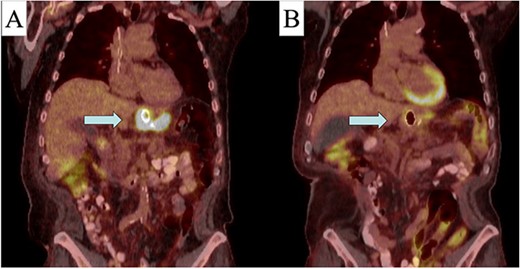

After a multidisciplinary discussion, the decision was made to proceed with neoadjuvant chemotherapy with folinic acid (leucovorin), fluorouracil (5-FU), and oxaliplatin (Eloxatin) (FOLFOX) and radiation therapy. A positron emission tomography (PET)-CT scan was obtained prior to therapy to monitor treatment response. Due to his symptomatic stenosis, an endoscopic stent was placed to assist with nutritional intake throughout the preoperative phase. Over the first month, FOLFOX was poorly tolerated, and he was switched to carboplatin-Taxol along with radiation therapy. Although tolerated, treatment was complicated by a contained perforation at the site of the mass 3 months into therapy. This was managed conservatively with antibiotics and parenteral nutrition. Through this management, a repeat PET-CT was obtained, which demonstrated good response to his initial therapy with decrease avidity at the GE junction (Fig. 3). Without any extra-regional spread and improvement in primary mass, the decision was made to proceed with operative resection.

Pre (A) and post (B) initial treatment PET-CT with response to neo-adjuvant therapy (area indicated by arrow).